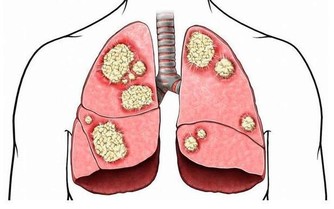

而尿騷味,則通常提示腎有問題了。

人體腎臟具有強大的代償功能,只要腎功能喪失不超過75%,仍能保持人體內環境的穩定。

所以,慢性腎衰病人早期常無明顯臨床症狀,往往容易誤診、漏診,使腎衰病人失去最佳的治療時機。

食慾減退和晨起噁心、嘔吐等,是慢性腎衰常見的早期表現。

另外,一些慢性腎衰病人還有一些特殊的臨床表現,如口腔內有氨的氣味,也就是你說的尿味,尿毒症病人更為明顯。

這是為什麼呢?

主要原因是,隨著腎功能的減退,腎臟的溶質清除率下降和某些肽類激素的滅活減少,造成多種毒素在血液和組織中蓄積,最常見的毒素就是尿素等。

在口腔中,因為唾液中的尿素被分解為氨,故病人呼出的氣體有尿味。

這種氣味的濃淡隨病情的進退而變化,在病情好轉時,口中尿味淡些,病情加重時尿味變濃。